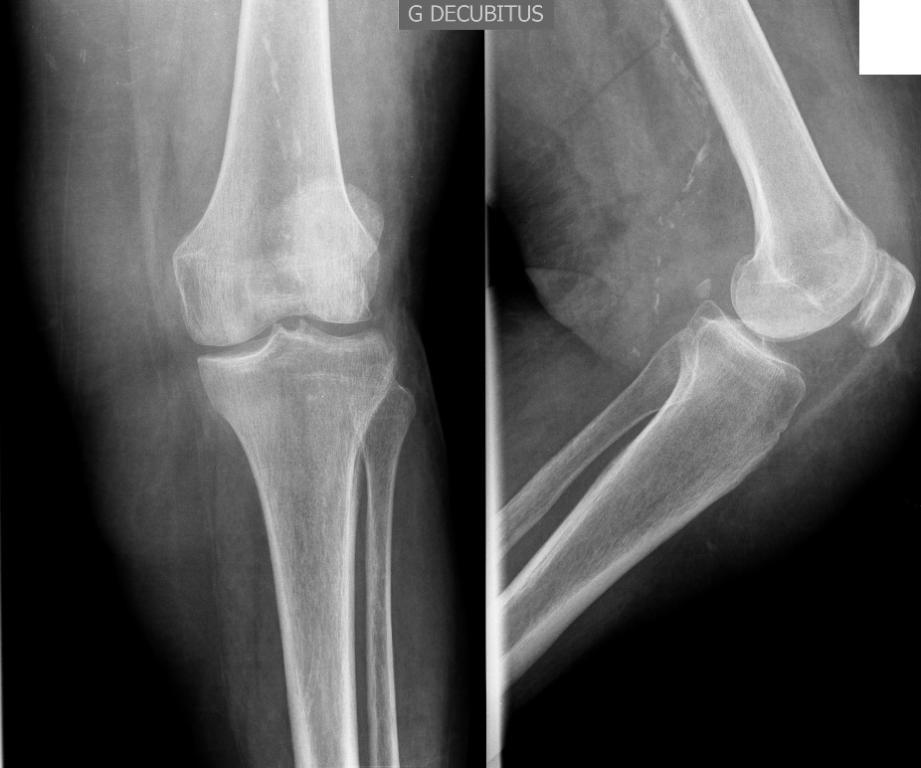

Vous prenez en charge dans votre consultation M. B., 53 ans, pour une douleur du genou gauche. Vous le suivez pour une hypertension artérielle équilibrée par hydrochlorothiazide, ainsi que pour un psoriasis du cuir chevelu non traité car peu invalidant.

La douleur est présente de manière croissante depuis 48 heures et, hier soir, il s’est senti fatigué et a eu des sueurs dans la nuit. Ce matin, la douleur était si intense qu’il lui était impossible de marcher. Il ne se rappelle pas avoir eu de traumatisme récent sur cette zone.